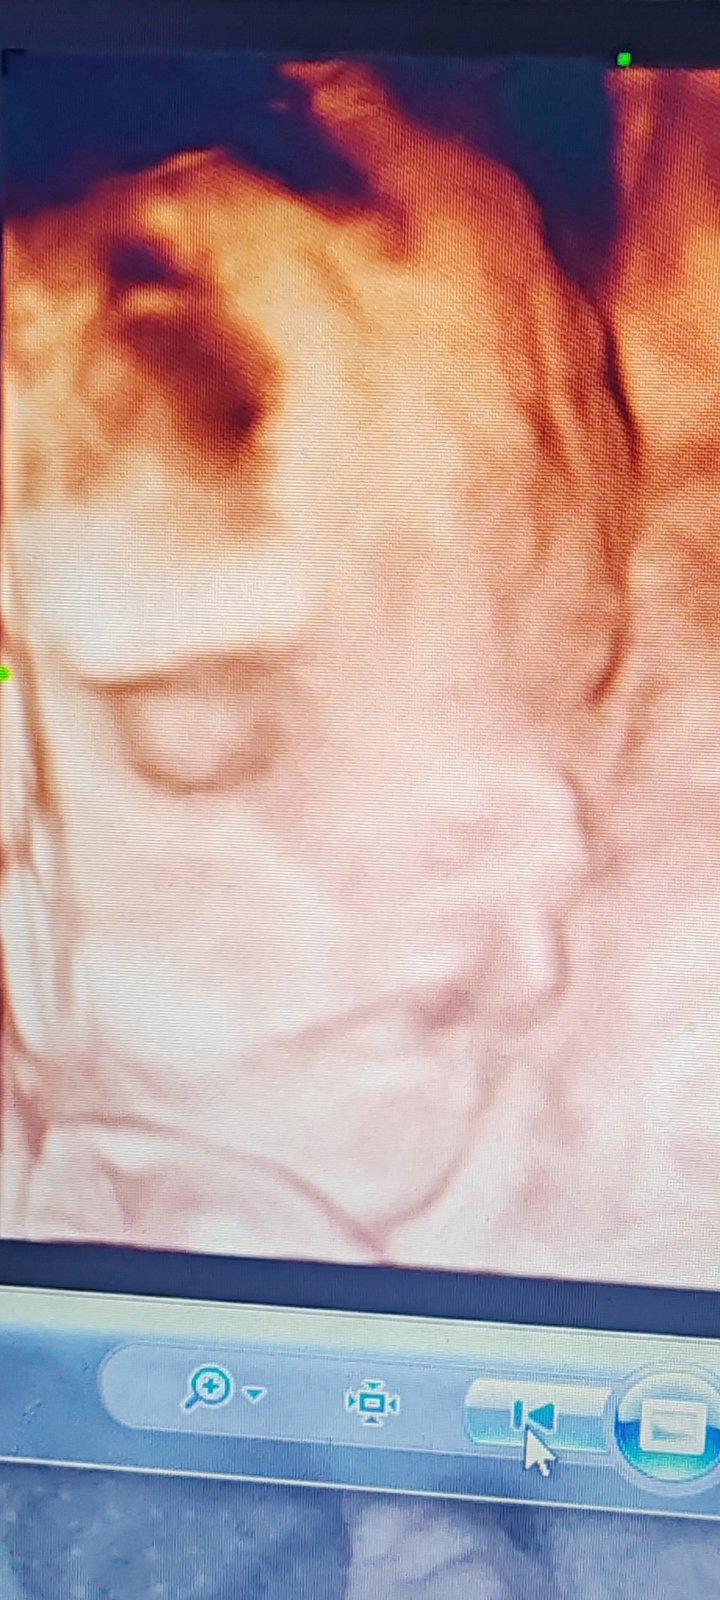

Jednu fotku som sem pridala. Urobte si názor sami. 😪 Ja už neviem

Ako som písala v prvej teme, neviem či tú fotku ešte kdesi vyhrabem ale proste na dcerinej fotke zo sona to fakt vyzeralo úplne akoby mala.dlhy roh uprostred cela ako jednorožec 😂 ..tú fotku sme rozdávali ak rodine takže sa natom celkom pobavili. Ale jasné že to bol tieň, doktor to ani nekomentoval kým som sa pri odchode nepýtala. Tie fotky sú naozaj kadejaké tiene atď, keď moja mohla mať roh na čele, to vaše malo podľa mňa čo si pamätám len tieň nad tou perou, mne to prišlo ako tá jamka čo máme všetci nad perou. Ja by som dr verila keď to pozeral na sone, ale ak máte pochybnosti choďte ešte k inému na 3D sono alebo tak.

@gabika029 Jaaaj. Lebo ja som bola na 3D scan tuším až v 32 týždni a to už bolo krásne vidieť tváričku, počkaj chvíľu a choď o niekoľko týždňov znova...neviem ako to je na Slovensku, ale v zahraničí som si za to platila, ja by som išla znova v 32-33 týždni a už budeš vidieť dieťa úplne ináč. Teraz aj ten nos vyzerá všeliako a aj tá pera, chápem tvoje obavy, nikto z nás ti tu nenapíše, že či je to OK alebo nie, lebo my nevieme..jedina rada odomňa, choď na 3D scan o niekoľko týždňov, sama uvidíš veľký rozdiel 😊 a potom sem napíš a daj nám vedieť ako to s bábom vyzerá. Držím prsty ❤️